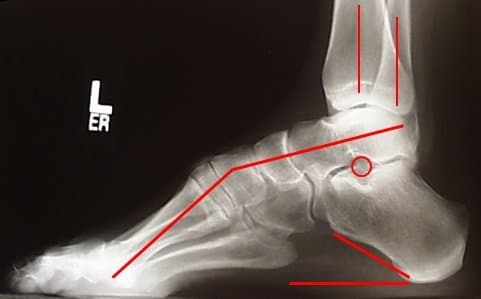

Слабость мышц и рефлексов ведет к нарушению походки. Человек падает, покачивается при ходьбе. Атрофия мелких мышечных волокон вызывает изменение формы стопы – свод увеличивается. Наблюдается деформация пальцев. В меньшей степени большого, пальцев, следующих за ним, в большей. Они сгибаются, начинают напоминать когти.

Подтверждение диагноза синдрома Шарко-Мари-Тута связано, прежде всего, с анализом неврологической симптоматики. Проверяется мускульная сила, сухожильные рефлексы, сенсорная сохранность, тремор. На приеме проверяется деформирование стопы, голени, кисти, позвоночника. Невролог в обязательном порядке проясняет историю появления симптомов, наличие признаков болезни в семье.